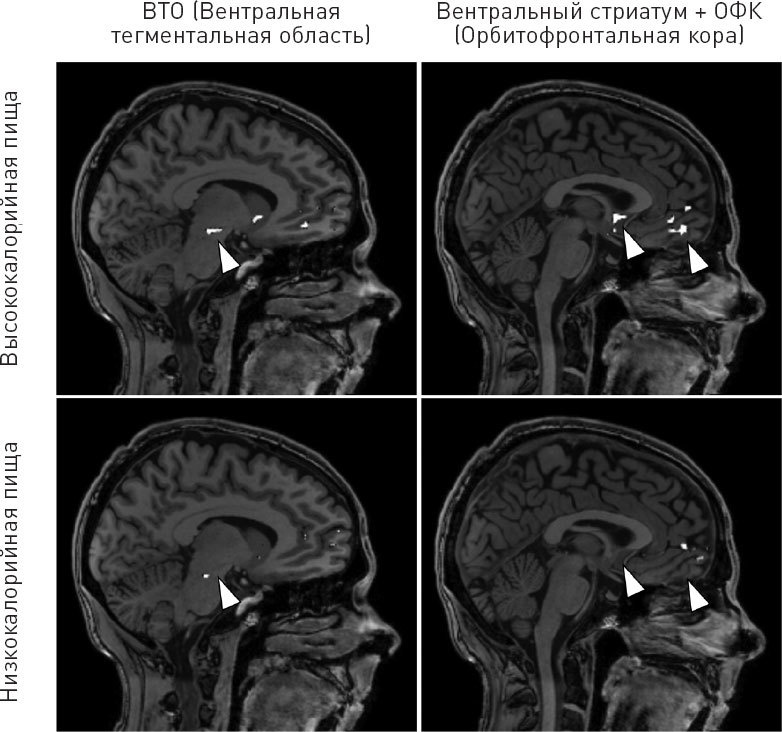

«Здесь мы видим классическую реакцию», – замечает Щур. Прежде всего она указывает вентральную тегментальную область. Если вы вспомните главы 2 и 3, то так называется отдел мозга, который выбрасывает дофамин в вентральный стриатум. Вентральная тегментальная область и вентральный стриатум отвечают за мотивацию и подкрепление, например в том случае, когда мы чувствуем аромат свежих шоколадных брауни. «Моя тегментальная область просто светится!» – вскричал я, не в силах сдержать удивление. Яркая цветная вспышка осветила тегментальную область – это значит, что дофаминовая система моего мозга очень обрадовалась изображению высококалорийного продукта. Черно-белый вариант снимка приведен на рис. 37 в верхнем левом углу.

Рис. 37. Снимки МРТ, на которых показана реакция автора книги на изображения высоко- и низкокалорийной пищи. Белые области указывают на активную работу отделов мозга. Стрелками отмечены ВТО (вентральная тегментальная область) (левый столбец) и ОФК (орбитофронтальная кора) (правый столбец). Обратите внимание на сильную реакцию мозга на изображения высококалорийной пищи. Все изображения сравнивались по принципу реакции мозга на изображения продуктов питания и изображения объектов, не связанных с пищей. Работа других отделов мозга, которые не участвуют в исследовании, на снимках скрыта. Особую благодарность автор выражает Эллен А. Щур, Сьюзан Дж. Мелхорн, Мэри К. Аскерн и Центру медицинских исследований и диагностики Вашингтонского университета.

Затем мы перенесли внимание на вентральный стриатум. Он также должен проявить активность, потому что реагирует на сигналы тегментальной области. На этот раз вспышка оказалась еще ярче. Вы можете убедиться этом, посмотрев на правый верхний снимок на рис. 37. «Это чудовищно», – подвела итог Щур.

Следом мы осмотрели орбитофронтальную кору (ОФК), область мозга, которая оценивает экономическую выгоду во время принятия решения. И снова яркое свечение (правый верхний угол рис. 37). «Вам необходимо принять решение», – объясняет Щур, – «и затем разработать план по добыче продовольствия».

Диагноз был совершенно ясен: голодный мозг требовал пищи. Очень настойчиво. И его совершенно не устраивала низкокалорийная еда, потому что разница на снимках была слишком очевидна. Активность мозга была крайне низкой, когда мне демонстрировали фотографии фруктов и овощей (два нижних изображения на рис. 37). «Когда мы испытываем чувство голода, нашему организму не интересна здоровая еда», – объясняет Щур. Напротив, наши инстинкты заставляют нас желать концентрированные, быстрые и легкодоступные калории. «Мы все вынуждены с этим бороться».